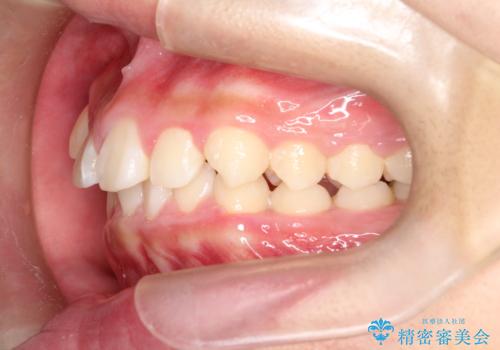

八重歯・歯並びのデコボコとディープバイトを改善した抜歯ワイヤー矯正症例

八重歯などの歯列のデコボコが綺麗に改善され、患者様にも大変喜んでいただけました。また、咬み合わせが深い「ディープバイト」も併せて改善し、見た目だけでなく機能面でもバランスの取れた咬合を獲得しています。